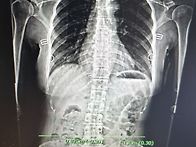

수련전과 수련후 골격의 ..

柔易(유이) 조혜원 22.07.12몸은 마음을 담는 그릇이라 합니다.그릇이 반듯해야 오장육부가 제자..